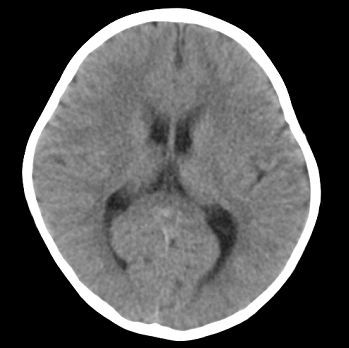

以下是引用22222222在2008-6-9 21:03:00的发言:[br]病灶周围见脑组织包绕,上部可见等或稍高密度壁环绕,壁且见小点钙化-----考虑皮样囊肿或表皮样囊肿可能,但侧脑室颞角内病灶不排除.